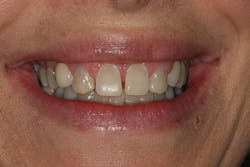

A 32-year-old white female presented for a cosmetic consultation. The patient reported that during her teenage years she had received orthodontic treatment to move her permanent maxillary canines mesially into the spaces that should have been occupied by her congenitally missing lateral incisors. She stated that her dentist, orthodontist, and oral surgeon had decided to place endosseous implants in the canine spaces due to the greater availability of bone in comparison to the bone available in the lateral positions (figure 1). As she grew older, she had become increasingly dissatisfied with the appearance of her smile and was seeking a more updated and esthetic solution (figure 2).

Figure 2